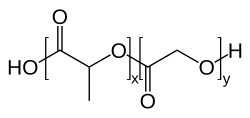

In den 1990er Jahren wurde in Versuchen mit Nanopartikeln, die aus biokompatiblen Polymeren aufgebaut sind, festgestellt, dass diese Partikel unter bestimmten Umständen in der Lage sind, die Blut-Hirn-Schranke zu passieren. Der Durchmesser dieser Partikel liegt üblicherweise bei 50 bis 300 nm. Die unfunktionalisierten, reinen Polymerpartikel sind in dieser Form nicht in der Lage durch das Endothel zum Gehirn transportiert zu werden. Der rezeptorvermittelte Transport ist nur durch eine spezielle Funktionalisierung, meist mit Polysorbat 80 oder Poloxameren,[70] möglich. Als Polymere werden meist Polylactide (PLA), Polylactid-co-Glycolid (PLGA) und verschiedene Polycyanoacrylate, wie beispielsweise Polybutylcyanoacrylat (PBCA),[71] verwendet, die pharmakologisch unbedenklich sind und für andere Anwendungen, beispielsweise als chirurgisches Nähmaterial, zugelassen sind. In die Partikel eingeschlossene Wirkstoffe können mittels rezeptorvermittelter Transzytose zum Gehirn transportiert werden.[72]

Die wesentlichen Voraussetzungen für die Hirngängigkeit der Nanopartikel ist – neben ihrer Größe – eine möglichst lange Zirkulationszeit im Blut und die passende Oberflächencharakteristik. Die Plasmahalbwertszeit wird meist durch eine PEGylierung erreicht und die Wechselwirkung am Endothel mit dem bereits beschriebenen Polysorbat.[73] Der genaue Transportmechanismus ist noch nicht endgültig geklärt. Der Polysorbat-Überzug der Partikel führt aber offensichtlich im Blutplasma zu einer Adsorption von Apolipoprotein E oder B an die Partikel. Dadurch werden die Nanopartikel als LDL-Mimetikum vom LDL-Rezeptor erkannt und in das Innere des Endothels transportiert. Danach wird der Wirkstoff entweder im Endothel freigesetzt, wodurch er per Diffusion zum Gehirn gelangen kann, oder die Partikel werden vollständig durch die abluminale Seite zum Gehirn ausgeschleust (Transzytose).[74]

Der nanopartikuläre Wirkstofftransport ist derzeit noch in der präklinischen Forschung. Im Tiermodell (Ratte) wurden vielversprechende Ergebnisse bei der Behandlung von transplantierten Glioblastomen erzielt. Dabei wurden die Partikel mit Doxorubicin beladen.[75] Der Transport von Doxorubicin in das Gehirn konnte dabei um den Faktor 60 gesteigert werden.[76] Die wegen der weitgehenden Undurchlässigkeit der Blut-Hirn-Schranke für Chemotherapeutika nur schwer zu realisierende Chemotherapie bei Gehirntumoren ist eines der Hauptziele bei der Entwicklung dieser nanopartikulären Wirkstoff-Träger-Systeme.[77]